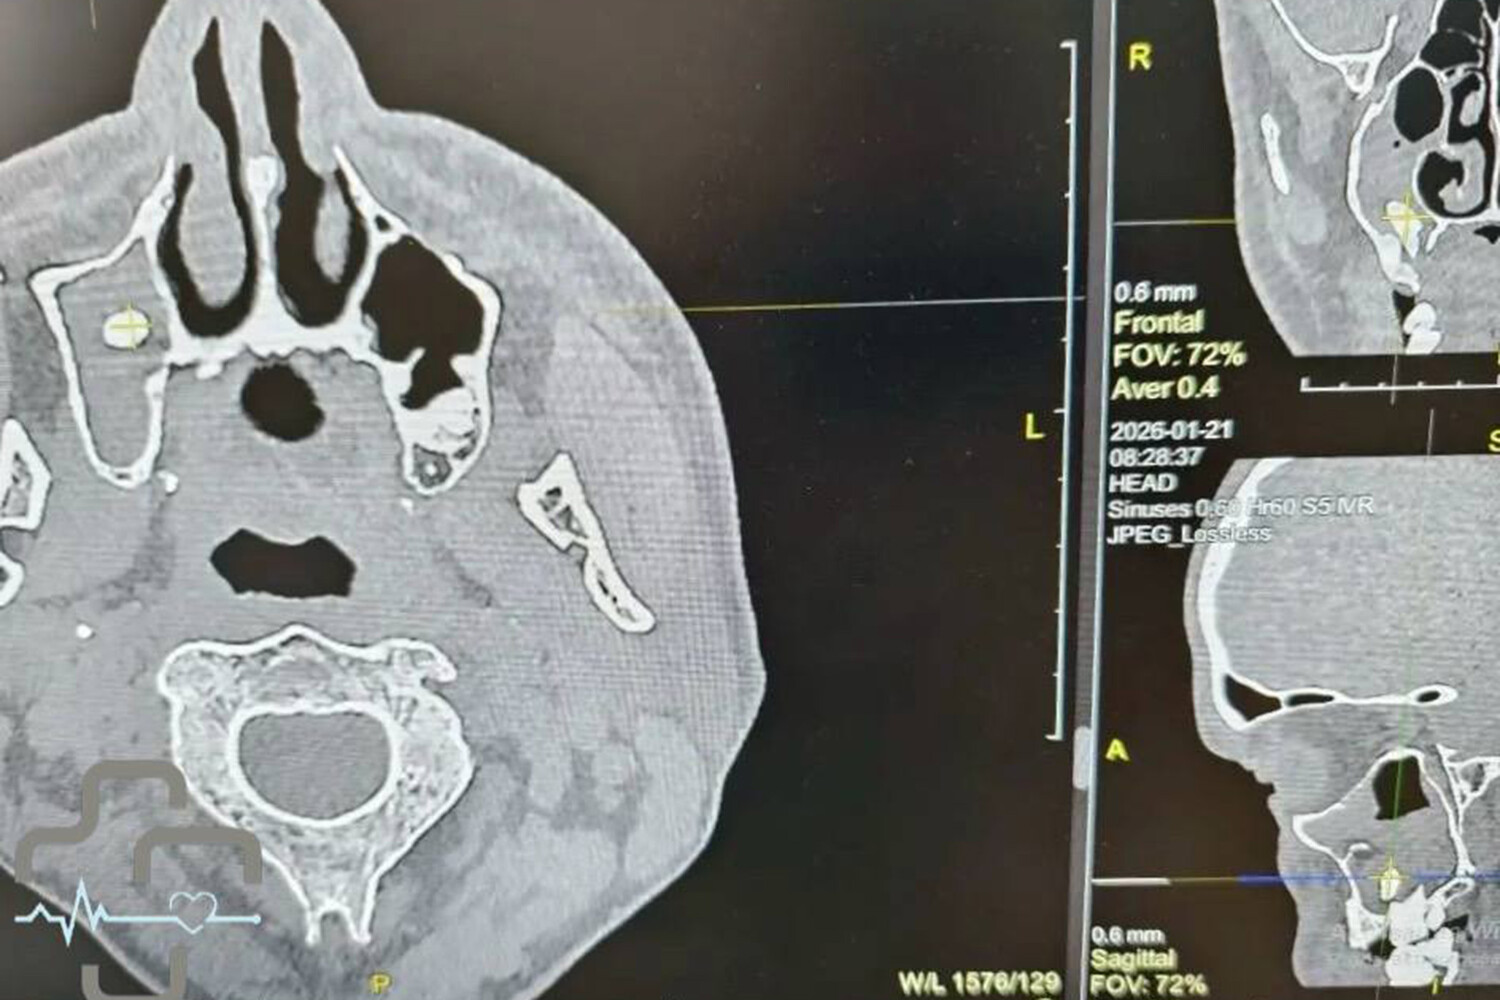

В Орске врачи обнаружили зуб в носовой пазухе у мужчины, который обратился в больницу с жалобами на затрудненное дыхание. Об этом сообщает городская больница Орска.

Диагностика показала, что в правой носовой пазухе мужчины находится зуб. Мужчина вспомнил, что незадолго до этого удалял зуб у стоматолога. Как пояснили врачи, во время процедуры могла нарушиться целостность костной перегородки между зубным рядом и пазухой, из-за чего зуб или его фрагмент сместились внутрь.

Заведующая лор-отделением с помощью эндоскопической стойки извлекла инородное тело, которое глубоко застряло в носу и мешало дыханию. Извлеченный зуб подарили пациенту на память.